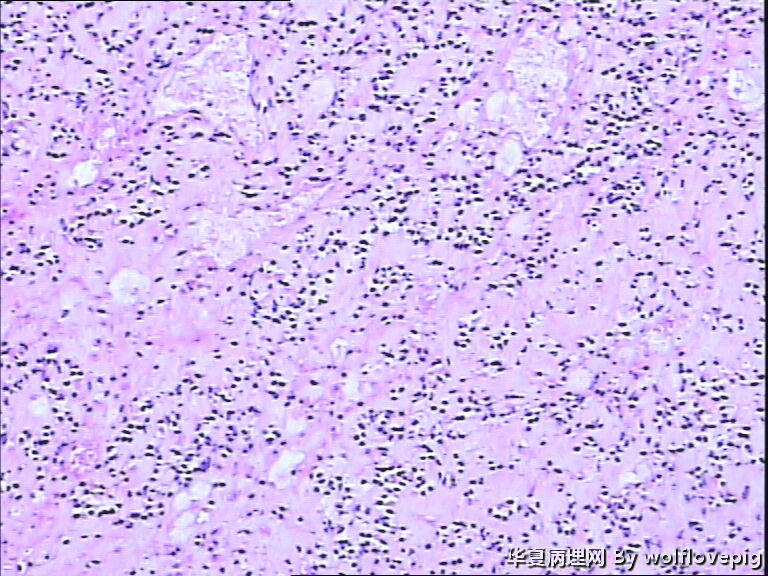

求助!肌瘤变性?

• 求助!肌瘤变性?图3

图3

平滑肌瘤伴间质玻璃样变性,像是冰冻的片子吧?》

上皮样平滑肌瘤,鉴别PECOMA

像平滑肌瘤玻璃变性

平滑肌瘤

上皮样平滑肌瘤

符合平滑肌瘤伴梗死,多取材寻找有无质软,肉质样变区,破碎的组织最麻烦,要慎重。